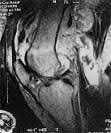

What is the most likely mechanism of failure for the patellar component shown: